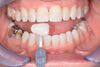

©2024 Cabinet dentaire du Dr Corinne DEBEAUVAIS - Chirurgien-dentiste